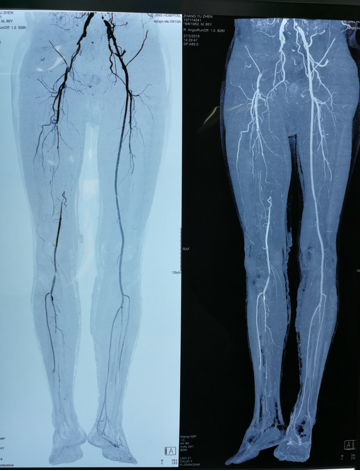

图:术前、术后CT

图:术前CT

图:下肢动脉硬化闭塞病变CT

图:下肢动脉硬化闭塞病